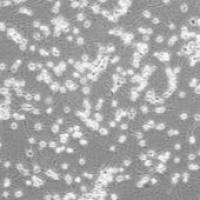

Human Pulmonary Fibroblasts (HPF)

Human Pulmonary Fibroblasts (HPF)人肺纤维原细胞

5x105 cells/瓶